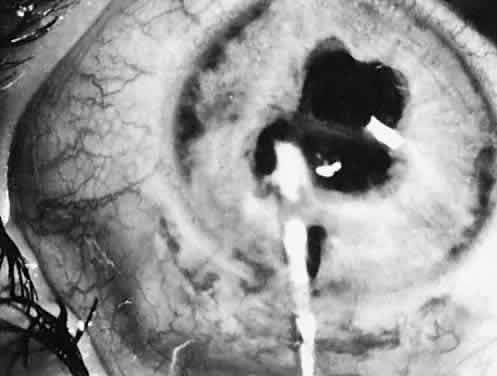

GLAUCOMA

Glaucoma can occur either in the early postoperative period or years after surgery. In a study of 65 patients with aphakic glaucoma, 87% were found to have glaucomas 2 years or more after lensectomy.51 Immediately after surgery, acute pressure elevation may be caused by viscoelastic material remaining in the anterior chamber, by pupillary block, or by synechial angle closure. The corneal scleral incision described usually can be closed without the aid of viscoelastic. If it is used, viscoelastic material should be removed from the anterior chamber before wound closure. Pupillary block glaucoma is uncommon, and when it occurs, it usually is related to a complicating factor.52 This cause of glaucoma is identified by a shallow anterior chamber, by an immobile pupil, or by visualization of posterior synechiae. Pupillary block is prevented by performing a peripheral iridectomy and by movement of the pupil after the operation with mydriatic drops.

Accurate measurement of IOP in children frequently requires sedation or examination with the patient under general anesthesia. Because of these difficulties, office measurements of the IOP are not performed routinely at each visit. Symptoms of pain, photophobia, irritability, and vomiting or signs of disc cupping, corneal clouding, or decreased tolerance of a contact lens should prompt measurement of the IOP. More subtle suggestions of glaucoma are increases in corneal diameter beyond normal growth and large myopic shifts in the refractive error. Because of the occurrence of late-onset glaucoma, it is important to measure the IOP every 6 to 12 months.

Eyes with pediatric cataracts appear to have an abnormal outflow facility and a propensity for open-angle glaucoma. Simon and colleagues52 reported glaucoma in 24% of eyes treated for cataracts and followed for at least 5 years. Johnson and Keech53 reported glaucoma in 32% of patients with PHPV-type cataracts (eight of 25) and the same 32% in patients with infantile cataract (15 of 47). The mean time of onset of glaucoma was 65 months and 47 months after surgery, respectively. Chrousos and associates38 found chronic glaucoma in 6.1% of treated eyes. Eyes with rubella, uveitis, or microphthalmia are particularly affected. A slightly more anteriorly placed incision and careful wound closure prevent iris-to-cornea adhesions. Figure 31 shows a gonioscopic view of an angle of a 5-year-old child in whom late-onset glaucoma developed after cataract surgery. Walton51 has described a near-constant (96%) but variable angle defect characterized by blockage of the trabecular meshwork by an acquired repositioning of the iris against the posterior trabecular meshwork.